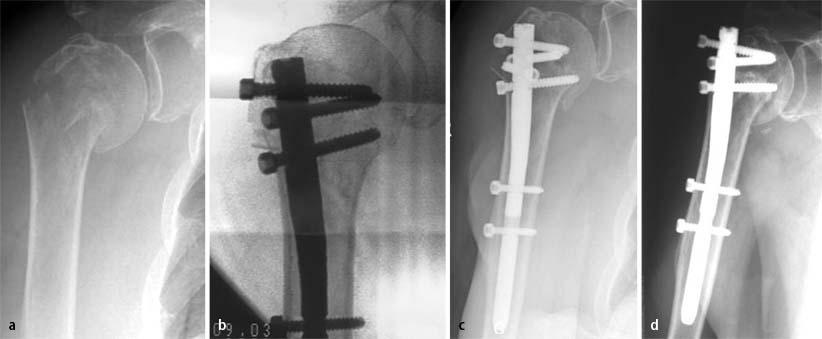

Seit Juni 2003 verwenden wir den T2-PHN (PHN: „proximal humeral nailing system“) der Fa. Stryker. Ähnlich mit anderen Systemen, z. B. dem Targon® PH der Fa. Aeskulap, handelt es sich um einen 150 mm langen Marknagel, der proximal mit 4 gekreuzten Verriegelungsoptionen in anatomisch sinnvollen Positionen versehen ist (Abb. 2). Die Löcher im Nagel verfügen über ein Innengewinde, wodurch eine winkelstabile und geführte Schraubenpositionierung möglich ist. Durch Nylonringe wird ein seitliches Ausdrehen der „Stellschrauben“ verhindert. Alle Verriegelungsschrauben werden über ein Zielsystem eingebracht. Das proximale Drittel des Nagels ist 10 mm stark und um 6° gegenüber dem 8 mm starken Schaft nach lateral gebogen. Andere Marknagelsysteme verfügen über einen geraden Marknagel ebenfalls mit geführten Verriegelungsschrauben, die durch Kunststoffringe gesichert werden.

Verriegelung des T2-PHN über Zielbügel, a Schema, b anatomische Schraubenposition, c in situ

Der T2-PHN steht auch als lange Version (220–300 mm Länge) zur Verfügung, um Frakturen mit Schaftbeteiligung versorgen zu können.